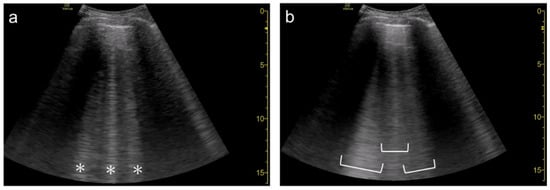

3.5. Simple Educational Materials

2. Generation of Vertical Artifacts